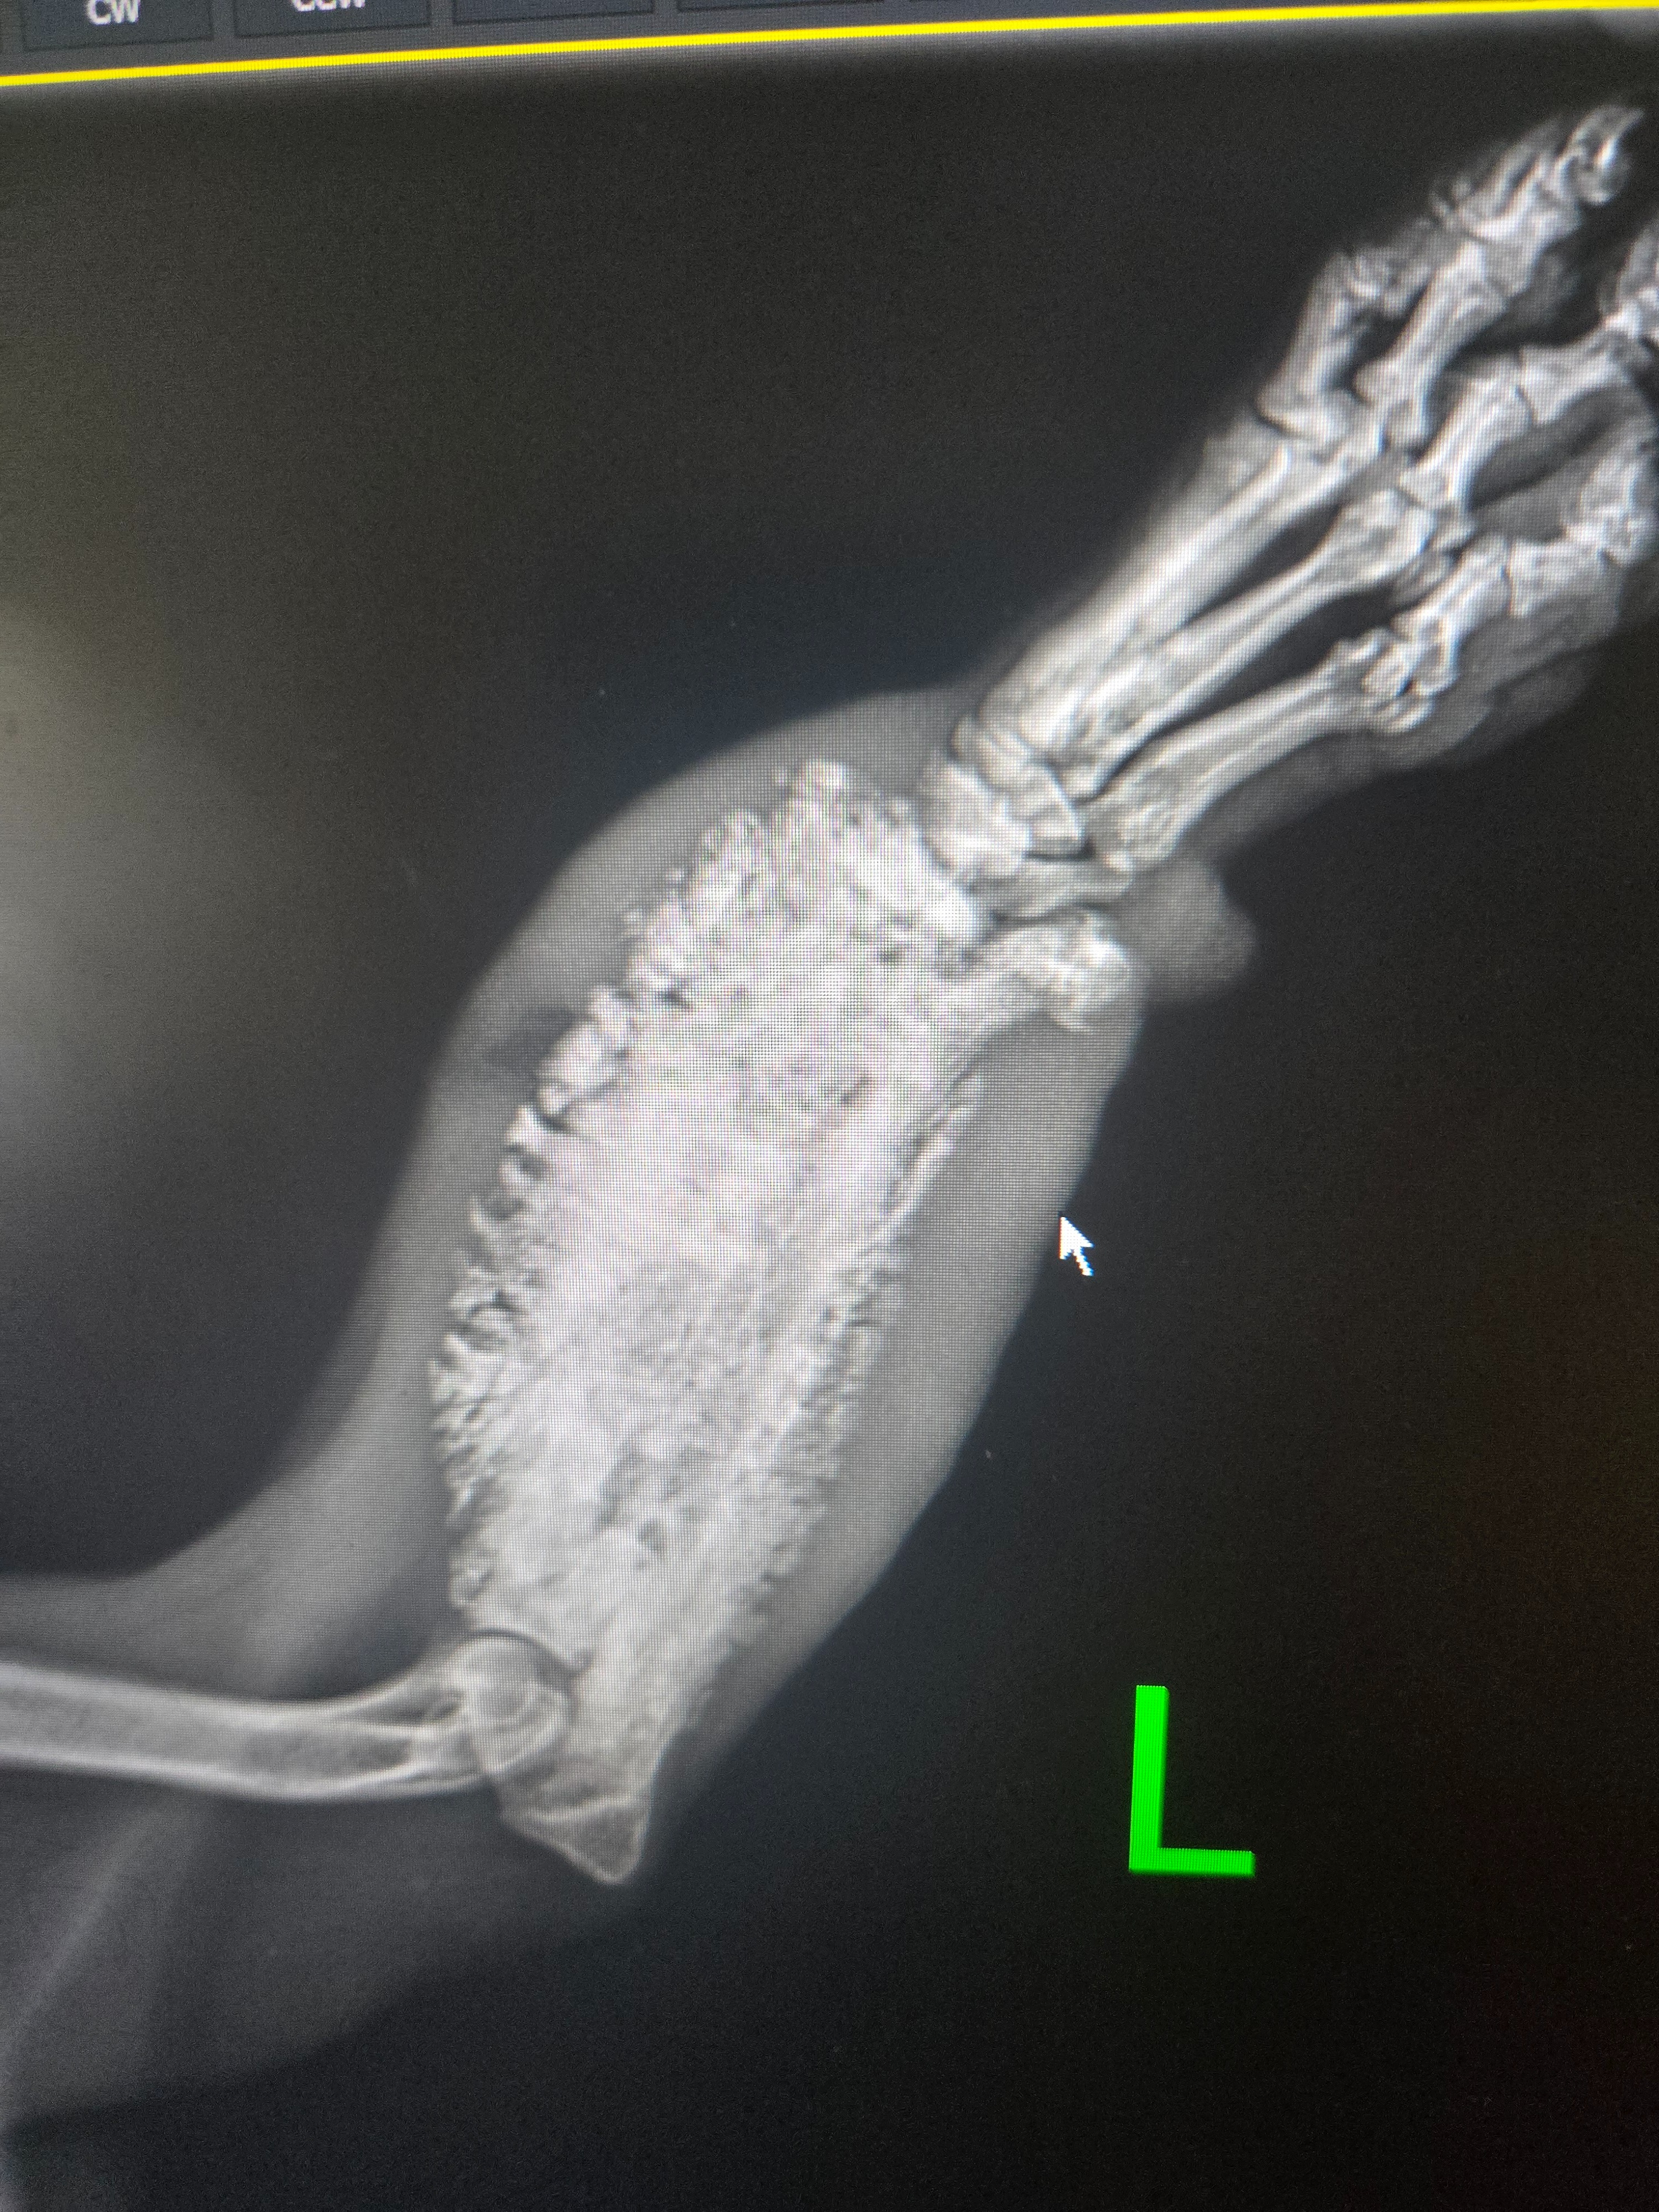

Found this dog twice. The first was up the street from my house , his leg was swollen at the time, but owner told me He was taking him to the vet. Then 2 months later, someone posted finding this little guy but now leg bigger and has an open green wound . Owners moved and left him behind. IVE already have spent 400.00 for medication and x rays.. I was given first a quote of 3,000 but found a vet that will do it for 1300.00 plus need to get this guy fixed. He is a sweet heart and runs around dragging his leg. The leg needs to be removed because the infection can spread.. just can't do this alone.